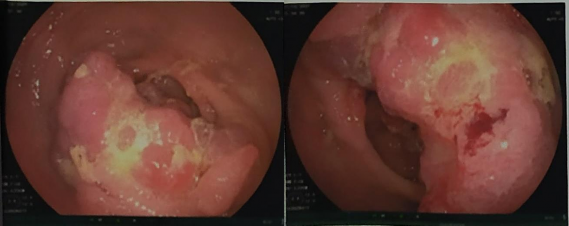

- Nội soi đại tràng

Kết quả:

Vị trí đại tràng gần góc gan có khối sùi lớn, kích thước 3x4cm, chiếm gần hết lòng đại tràng. Bề mặt sần sùi.